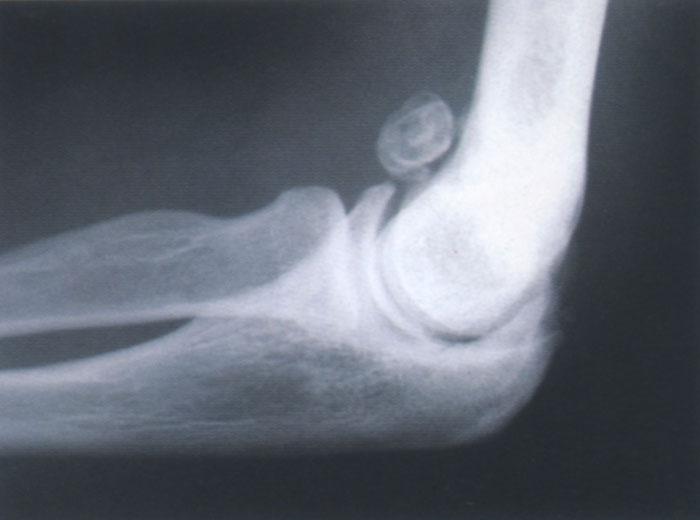

图1

游离体取出(图1)。